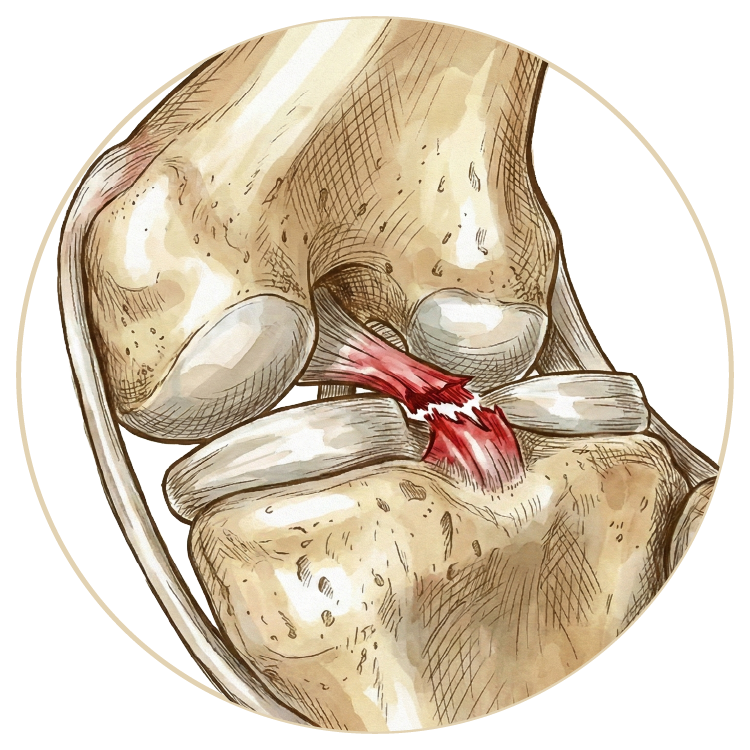

Ön Çapraz Bağ Ameliyatı

Arka Çapraz Bağ Ameliyatı